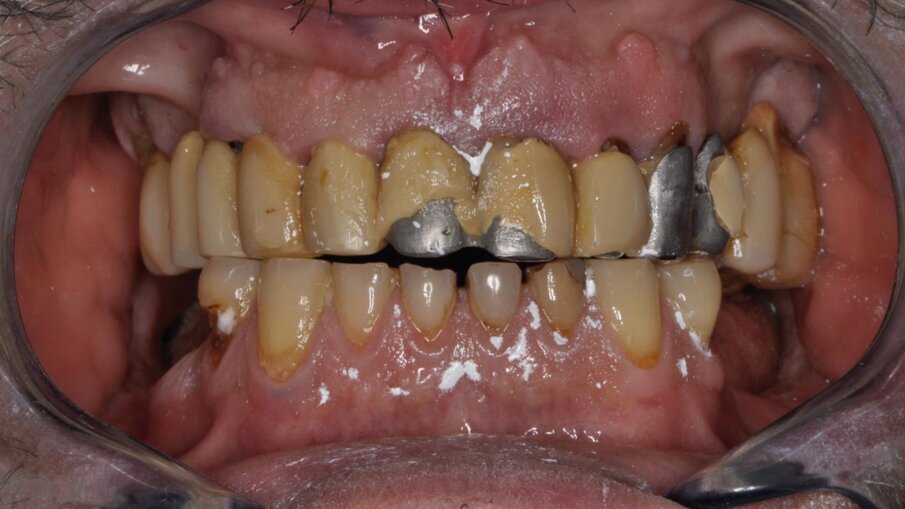

Nel 2017, un paziente si è presentato in studio con gravi lesioni cariose che interessavano gli elementi dentari 43, 42, 41, 31, 32 e 33; lesioni cervicali di V classe, esposizione radicolare, e marcata abrasione dentaria generalizzata, particolarmente evidente nel gruppo frontale anteriore, associata a una riduzione della funzione nei settori posteriori.

Il paziente lamentava l’aspetto estetico e la riduzione della capacità masticatoria, sottolineando l’impossibilità di affrontare molteplici visite di riabilitazione protesica (Fig. 1). Si è proceduto con una seduta di igiene orale approfondita, esami radiografici endorali e una scansione intraorale per registrare in dettaglio lo stato iniziale del paziente. Successivamente, sono state rimosse le lesioni cariose dagli elementi affetti, gravemente compromessi ma recuperabili (Fig. 2). È stato proposto al paziente un trattamento chairside in grado di risolvere i problemi funzionali ed estetici in poche ore, utilizzando preparazioni minimamente invasive e la tecnica di stampa dei restauri eseguita direttamente in studio. Dopo l’accettazione del paziente, sono state effettuate preparazioni mini-invasive, levigate e lucidate con strumenti abrasivi siliconici a grana decrescente (media/fine). Ultimate le preparazioni e verificate le condizioni dei tessuti molli e la visibilità dei margini cervicali, si è proceduto con la scansione intraorale delle arcate e la registrazione dei rapporti occlusali (Fig. 3).

Fig. 1_Foto frontale delle arcate: situazione prima visita.